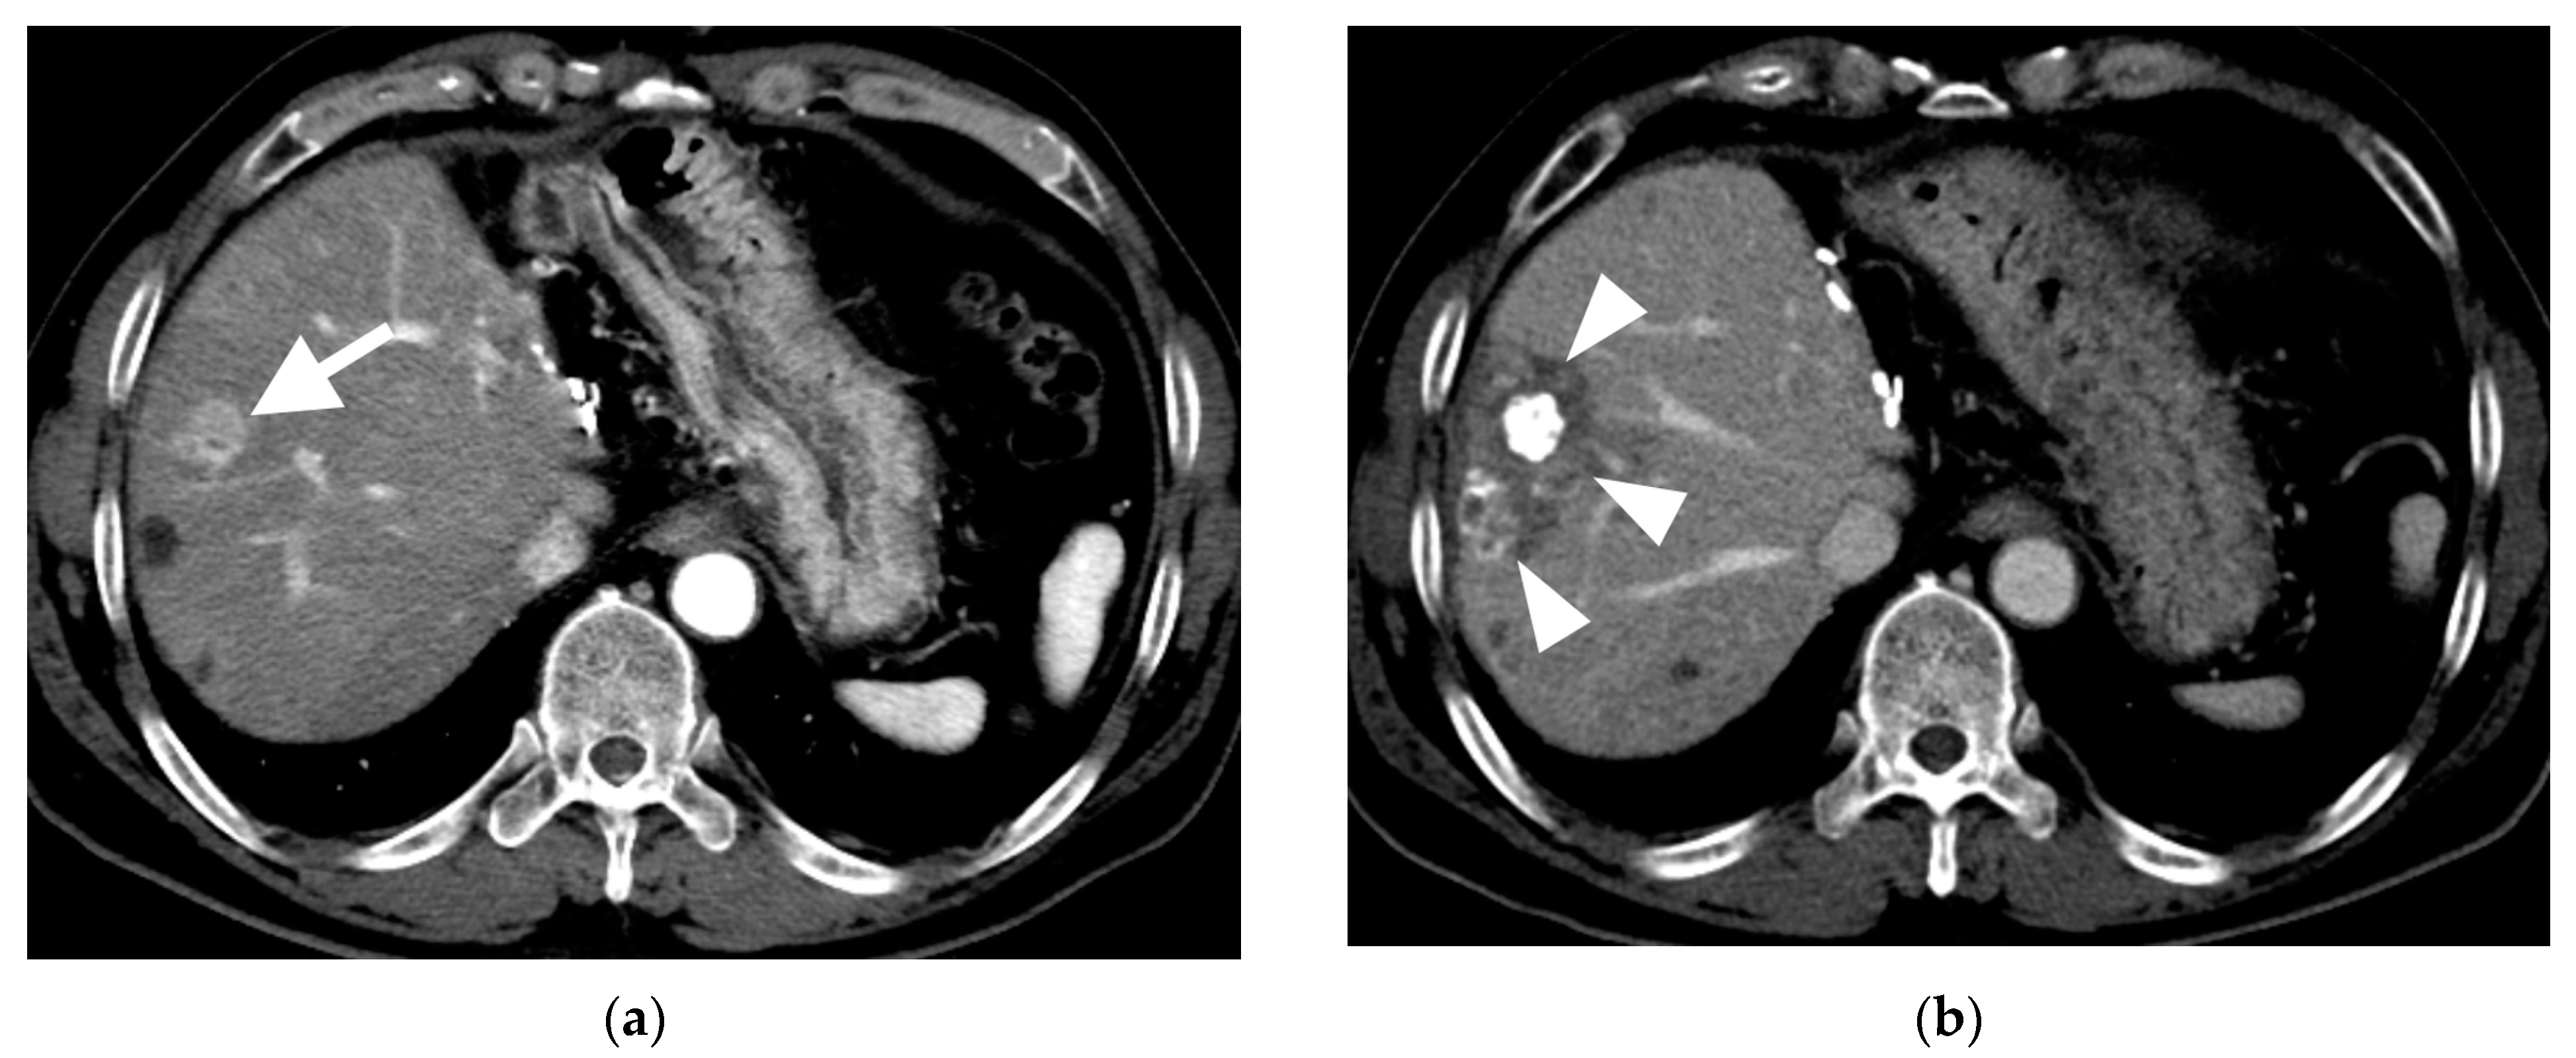

3.3. Local Recurrence